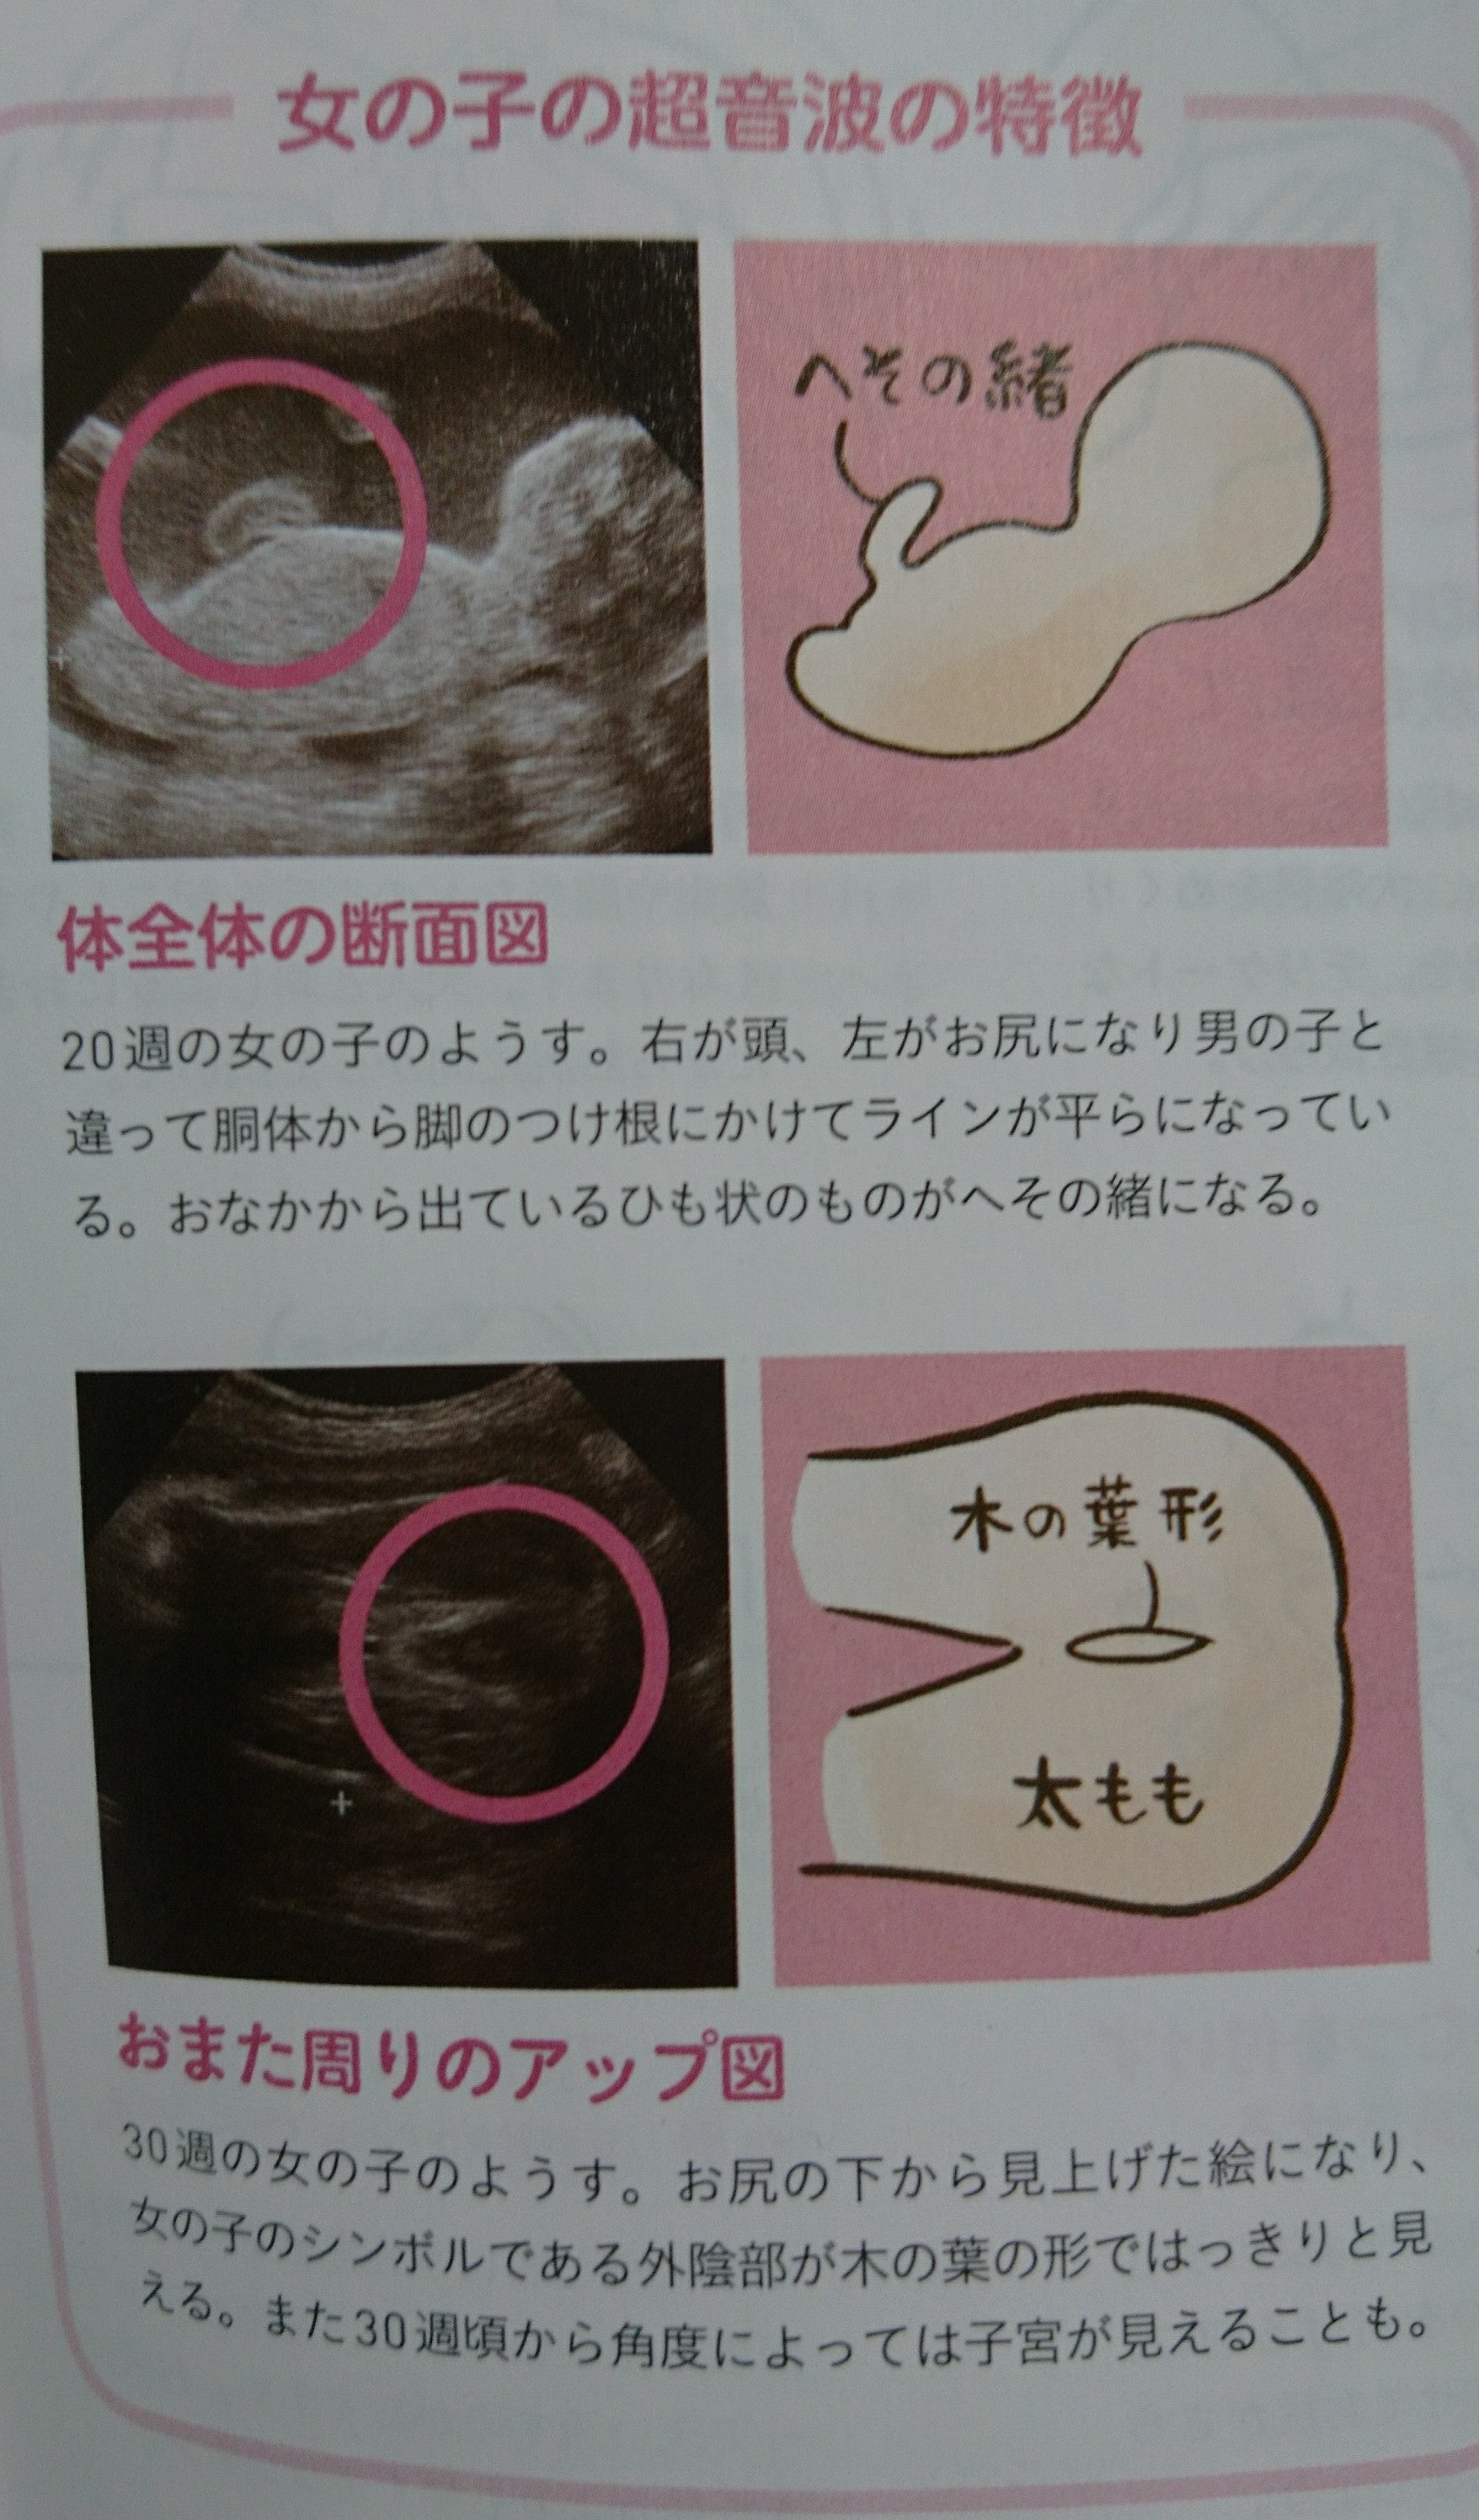

エコー 女の子 木の葉. 妊娠 - エコーでみる赤ちゃんの性別(山が二つで女の子?) 妊娠34週に入りました。 先日までまだ性別が確定していなかったのですが、 エコーの結果、先生に女の子だと言われました。 股の下からの画像では... 女の子の証拠エコー「木の葉形」を 41歳5人目にして 初めて知ったjunなのでした☆ でも思い出してみると 先月に男の子って言われて 「妊娠7ヶ月 エコー 男の子 間違い」 とかいろいろググって見てる時に 「木の葉」ってキーワードは見た気がする!. 妊娠24週ってどんな時期?! エコーで赤ちゃんの性別が確定できました♡女の子の場合でも断定できる!葉っぱマークや子宮が見えるって本当?? そしてツワリも終わって気をつけたいのが体重管理!! 妊娠中の体重増加の目安って?ツワリで減った場合は、どの時点の体重から考えるべき?.

東京 テアトル 評判~杖 イラスト 無料;. 残念ながら我が家に女の子はいないので、とてもわかりやすい画像をゼクシィbabyよりお借りしました。 女の子の場合、 会陰部に”木の葉マーク”や”コーヒー豆”のような真ん中に何かしらの線が入っていることで判断 されます。. 解決済み 質問日時: 2014年2月2日 18:43 回答数: 1 閲覧数: 671.

女の子 の場合は、突起物はなく、 太ももの間に 木の葉のようなもの が見えます。 また、子宮と膀胱がふたつの黒い点として エコー写真に写ります。 ※女の子に恵まれれば、いつか写真参考アップしますね٩(•౪• ٩).